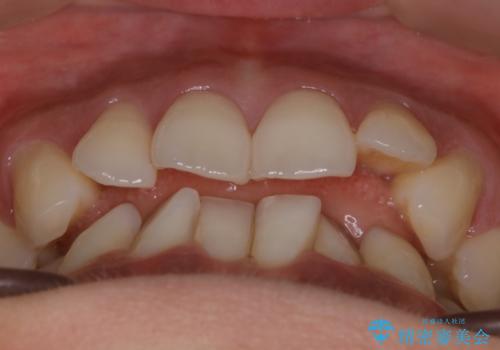

- 歯のガタつきによる見栄えや清掃困難を主訴にご来院されました。

左側の噛み合わせは上の歯が前方に寄ってきてしまっていることが原因のズレがありました。

ガタつき自体は歯列の幅の拡大やディスキング(IPR)でほとんど解消可能でしたが、噛み合わせのズレは歯の移動が必要だったため、左上にマイクロインプラントを使用し噛み合わせの改善とガタつきの解消を同時に進めるという方針をとりました。